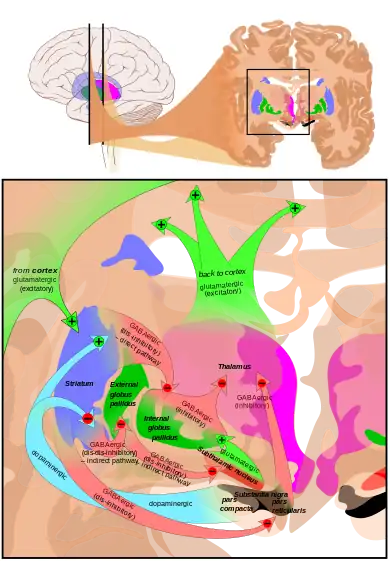

Dopamine-loops in Parkinson's disease | |

The globus pallidus (GP), also known as paleostriatum or dorsal pallidum,[1] is a subcortical structure of the brain. It consists of two adjacent segments, one external, known in rodents simply as the globus pallidus, and one internal, known in rodents as the entopeduncular nucleus. It is part of the telencephalon, but retains close functional ties with the subthalamus in the diencephalon – both of which are part of the extrapyramidal motor system.[2] The globus pallidus is a major component of the basal ganglia, with principal inputs from the striatum, and principal direct outputs to the thalamus and the substantia nigra. The latter is made up of similar neuronal elements, has similar afferents from the striatum, similar projections to the thalamus, and has a similar synaptology. Neither receives direct cortical afferents, and both receive substantial additional inputs from the intralaminar thalamus.

The globus pallidus is a structure in the brain involved in the regulation of voluntary movement.[7] It is part of the basal ganglia, which, among many other functions, regulate movements that occur on the subconscious level. If the globus pallidus is damaged, it can cause movement disorders, as its regulatory function will be impaired. There may be cases in which damage is deliberately induced, as in a procedure known as a pallidotomy,[8] in which a lesion is created to reduce involuntary muscle tremors. When it comes to regulation of movement, the globus pallidus has a primarily inhibitory action that balances the excitatory action of the cerebellum. These two systems evolved to work in harmony with each other to allow smooth and controlled movements. Imbalances can result in tremors, jerks, and other movement problems, as seen in some people with progressive neurological disorders characterized by symptoms like tremors. The basal ganglia acts on a subconscious level, requiring no conscious effort to function. When someone makes a decision to engage in an activity such as petting a dog, for example, these structures help to regulate the movement to make it as smooth as possible, and to respond to sensory feedback. Likewise, the globus pallidus is involved in the constant subtle regulation of movement that allows people to walk and engage in a wide variety of other activities with a minimal level of disruption.

Common afferents

The two parts receive successively a large quantity of GABAergic axonal terminal arborisations from the striatum through the dense striato-pallidonigral bundle. The synaptology is very peculiar (see primate basal ganglia system).[5][6] The striatal afferents contribute more than 90% of synapses. The two pallidal nuclei receive dopaminergic axons from the pars compacta of the substantia nigra.

Pathway

This area of the basal ganglia receives input from another area, called the striatum, which has two parts, the caudate nucleus and the putamen. This data is routed to the thalamus, either directly or indirectly. In the case of the interna, one area of the globus pallidus, the structure can feed directly to the thalamus. The externa, which lies on the outside of this structure, feeds information to the interna, where it can be passed on to the thalamus.